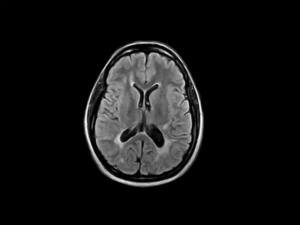

Similarly, S-scan is engineered specifically for efficient MSK imaging, offering a comprehensive solution for evaluating musculoskeletal anatomy and pathology. With real-time positioning capabilities and intuitive user interfaces, it streamlines imaging protocols, ensuring swift acquisition of high-quality images necessary for accurate diagnoses. Employing specialized MSK MRI protocols, S-scan enables clinicians to assess ligaments, tendons, and muscles with exceptional detail, enhancing diagnostic confidence and treatment planning in orthopedic practice.

S-scan – FLAIR Axial Head